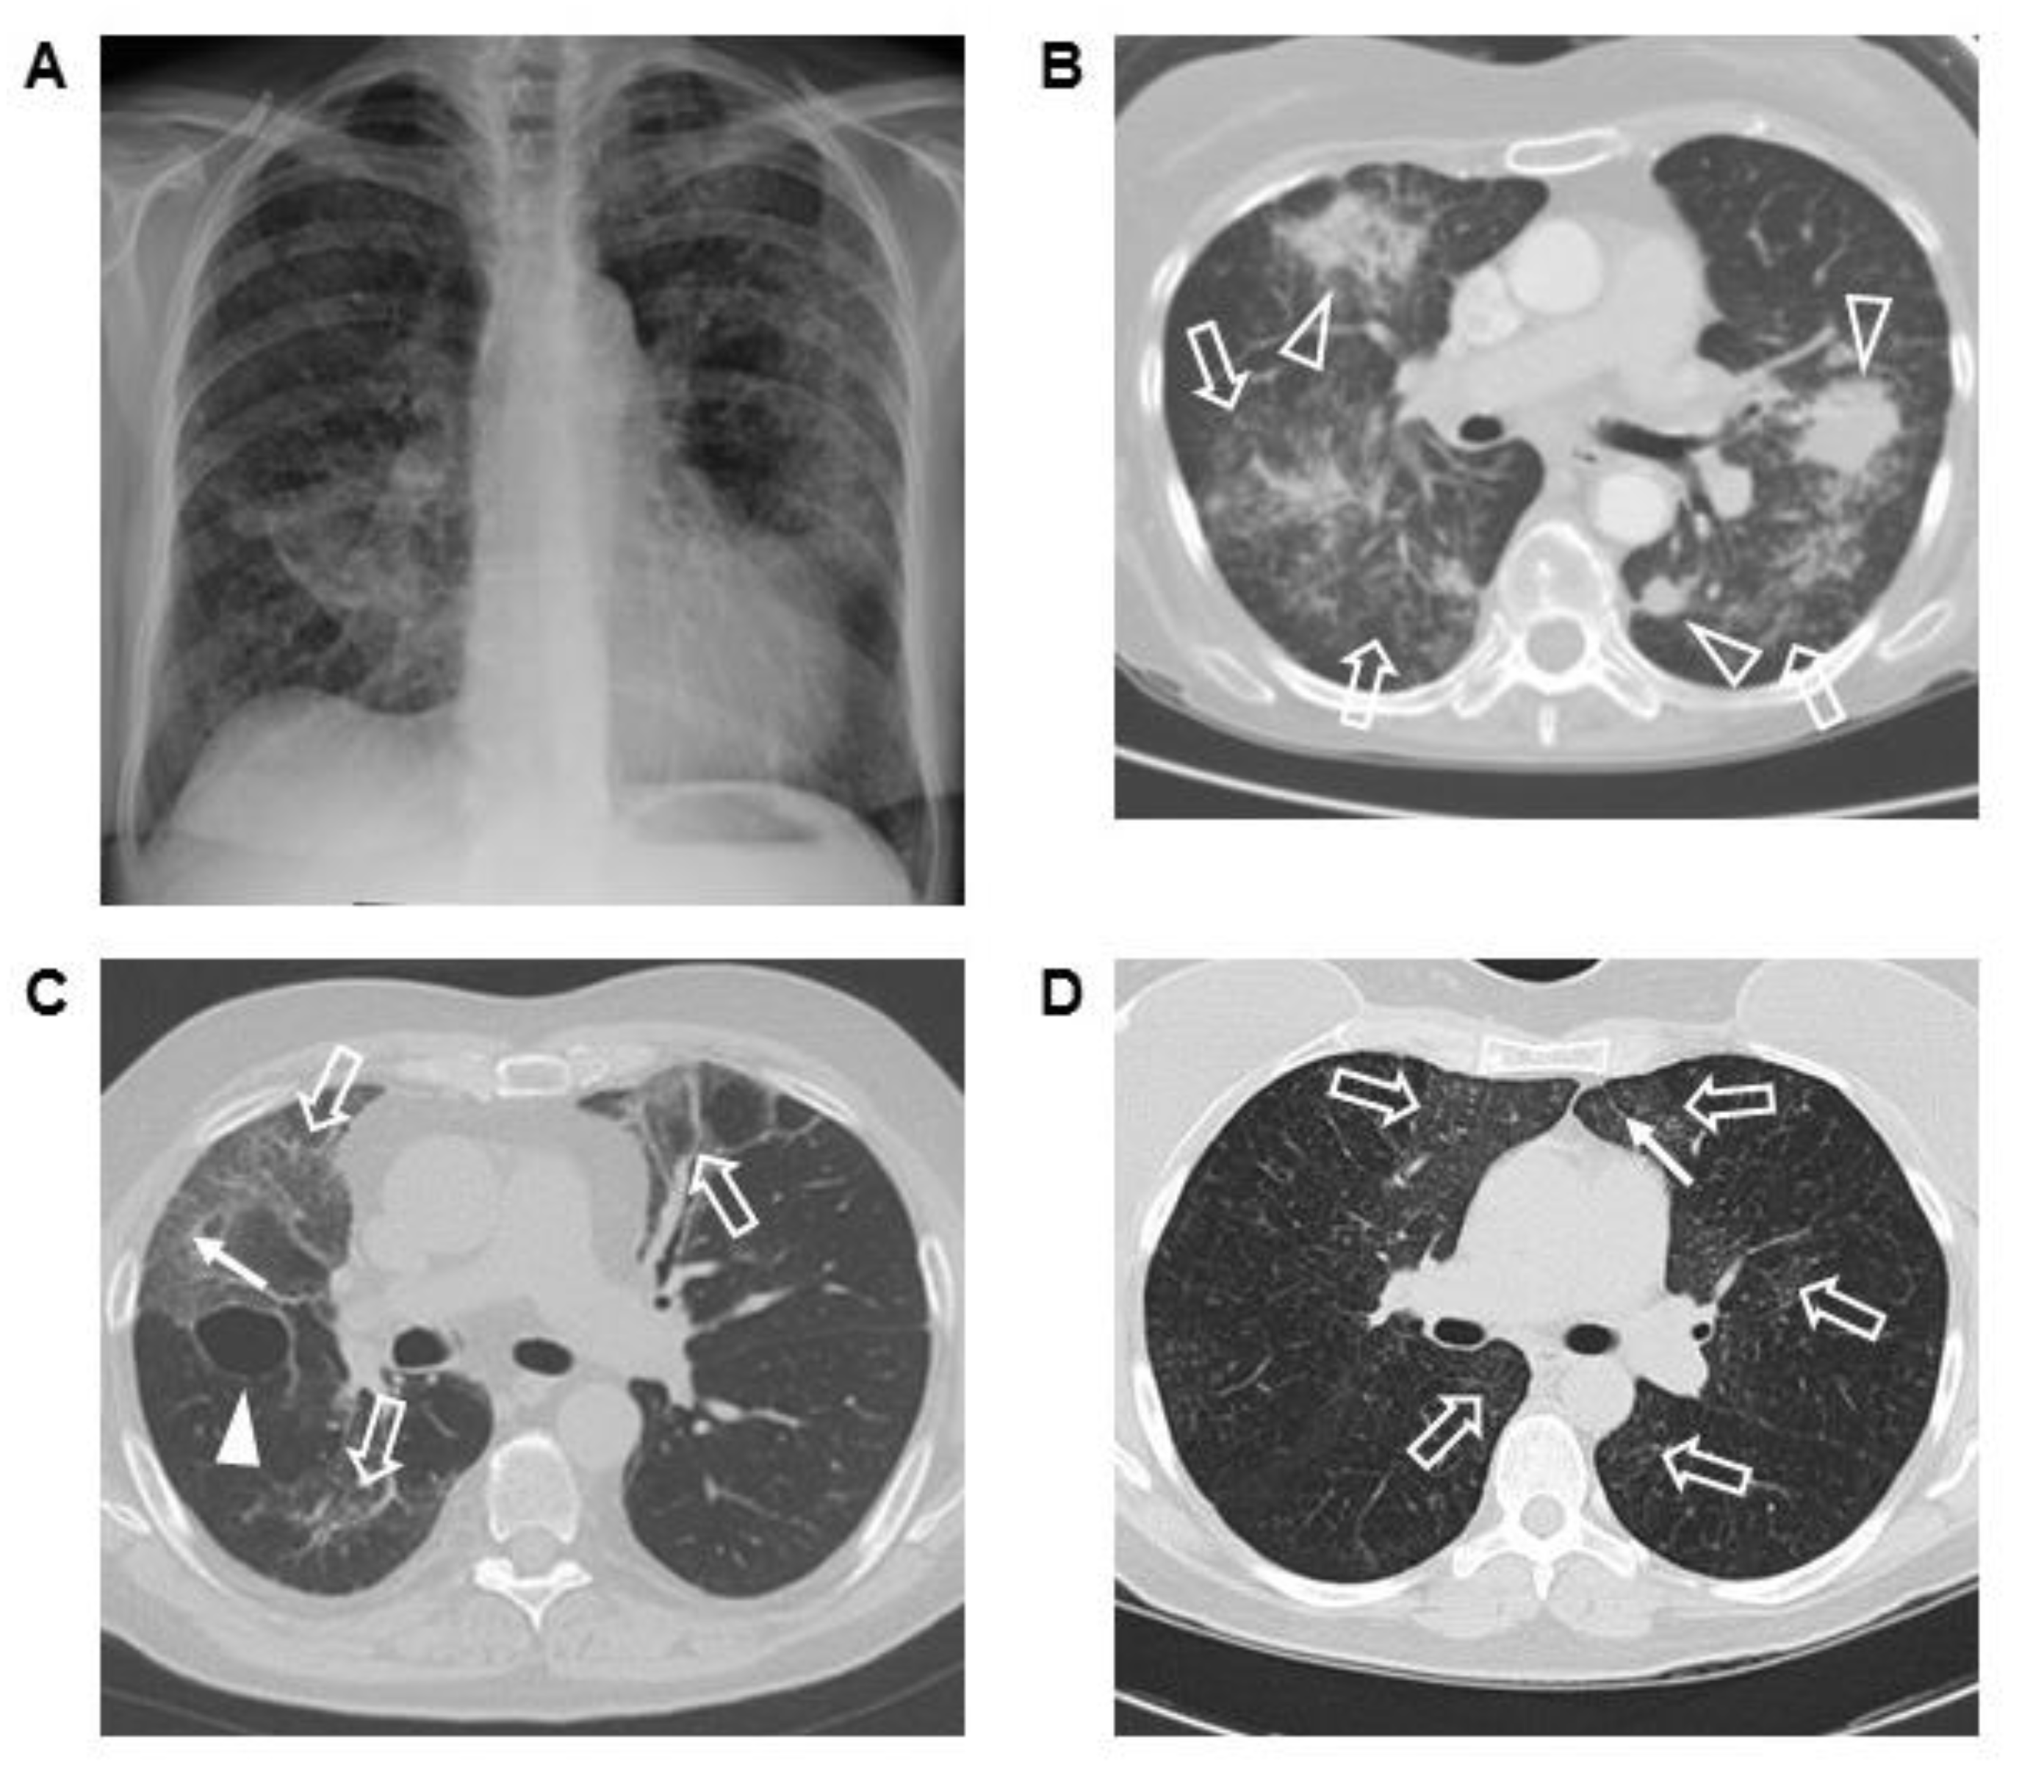

3.4. Corresponding Radiographic and Histopathologic Findings